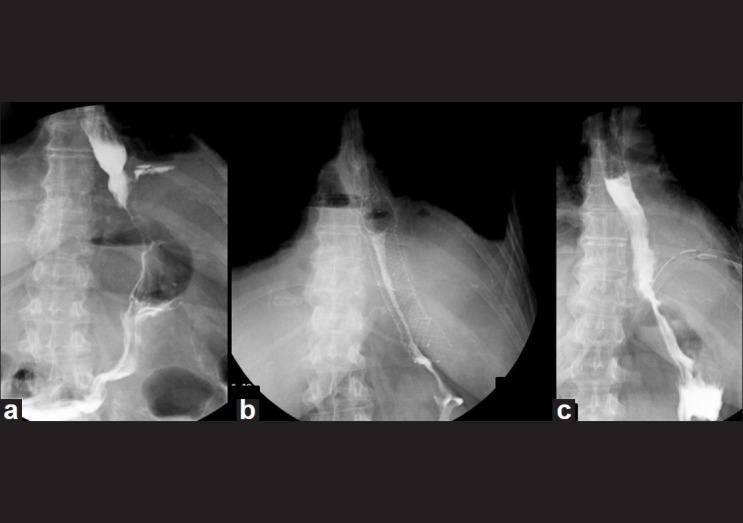

Fully covered self-expanding metal stent (SEMS) placement has been successfully described for the treatment of malignant and benign conditions. The aim of this study is to evaluate our experience of fully covered SEMS placement for post-operative foregut leaks.

Retrospective analysis was done for indications, outcomes and complications of SEMS placed in homogeneous population of 15 patients with post-operative foregut leaks in our tertiary-care centre from December 2008 to December 2010. Stent placement and removal, clinical and radiological evidence of leak healing, migration and other complications were the main outcomes analyzed.

Twenty-three HANAROSTENT(®) SEMS were successfully placed in 14/15 patients (93%) with post-operative foregut leaks for an average duration of 28.73 days (range=1-42 days) per patient and 18.73 days per SEMS. Three (20%) patients needed to be re-stented for persistent leaks ultimately resulting in leak closure. Total 5/15 (33.33%) patients and 7/23 (30.43%) stents showed migration; 5/7 (71.42%) migrated stents could be retrieved endoscopically. There were mucosal ulceration in 2/15 (13.33%) and pain in 1/15 (6.66%) patients.

Stenting with SEMS seems to be a feasible option as a primary care modality for patients with post-operative foregut leaks.